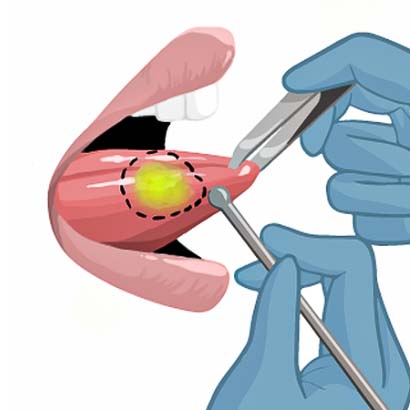

Light Guided Surgery uses fluorescent markers that make the tumor light up during surgery. We are currently investigating if this will help surgeons to remove tumor tissue.

Today surgeons rely on their vision and touch to assess what should be removed during tumor resection. However, 15-30% of all head and neck cancer patients leave the operation room with tumor cells left behind. For these patients, the chances of tumor recurrence are high and overall survival low.

We are currently investigating if Light Guided Surgery could help solve this problem.

1) Infusion of fluorescent dye that reaches the tumor.

2) The tumor will light up with a special camera during surgery.

3) The surgeon will outline the tumor.

4) The surgeon will remove the tumor.

5) After tumor resection, the surgeon checks the wound bed for remaining cancer.

6) The tumor is removed.